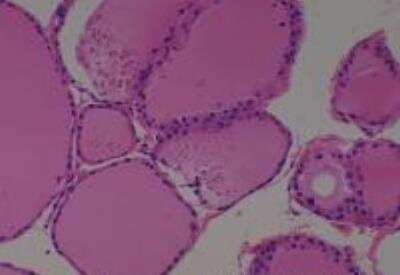

Scientific Data Images for Human Multi Tissue MicroArray (Normal Adjacent)